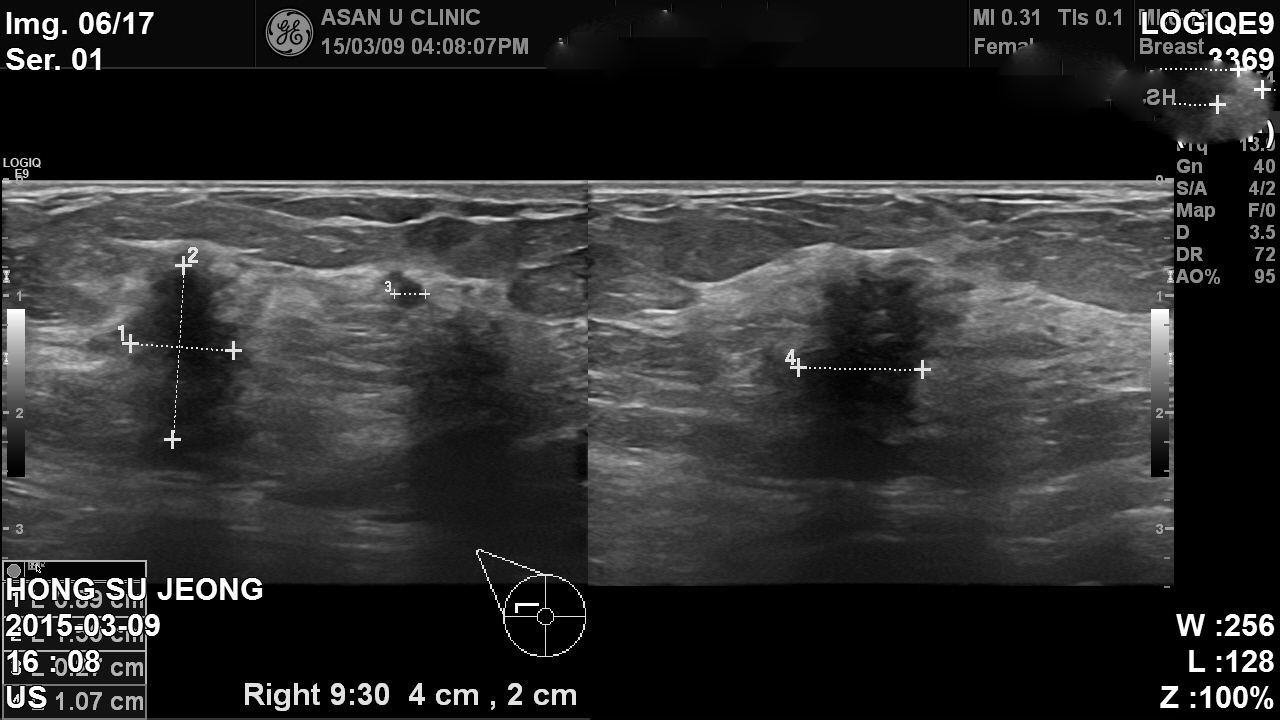

아산유외과 개원후 230번째 유방암진단

공단검진상 이상소견으로 내원함

유방이 치밀한 상태가 아니어서 혹이 작지만 만져짐.

조직검사상 침윤성 유관암.

주변에도 암의심 병변있으나 크기작음.